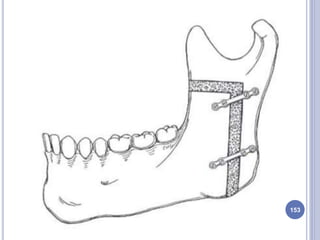

7. INTRAORAL MODIFIED SAGITTAL SPLIT

OSTEOTOMY

 Also called as - Bilateral Sagittal Split Osteotomy

 It is performed on the mandibular ramus and body.

 First described by Obwegesser and Trauner and later

modified by Dal Pont, Hunsuck and Epker.

 Transoral incision, similar to that used for IVRO.

 The osteotomy splits the ramus & the posterior body of the

mandible sagittally, which allows either setback or

advancement.

 This is a highly cosmetic procedure, as it is done intraorally,

plus, there is broader bony contact of the osteotomised

segments, ensuring good healing.

Drawback:

* High level of operative skill is required.

* Experience to minimize the surgical complication.